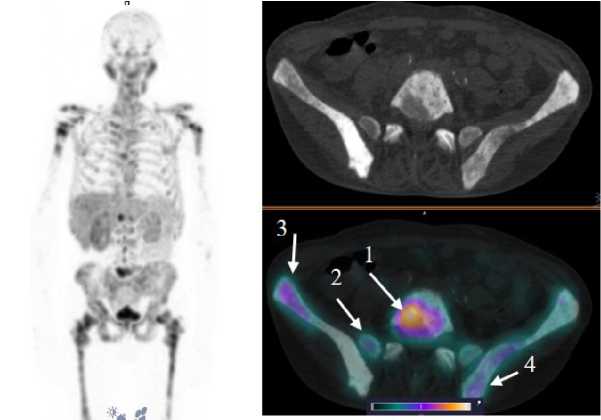

У 4 пациентов из обследованных в анамнезе было проведено радикальное лечение первичной опухоли в объеме либо простатэктомии (n = 2), либо дистанционной лучевой терапии (n = 2), по результатам динамического наблюдения данных за рецидив заболевания, продолженный рост опухоли получено не было, накопления [99mTc]Tc-HYNIC-PSMA в ложе предстательной железы (ПЖ) также не наблюдалось. У 6 пациентов ПЖ не была удалена, у одного из этих пациентов начата антиандрогенная терапия, еще у одного пациента диагностировано прогрессирование заболевания после 2 линии терапии — у всех больных отмечалось очаговое накопление РФЛП в предстательной железе (рис. 3). Для количественной оценки интенсивности накопления индикатора использовался показатель стандартизированного уровня накопления (SUV, the standardized uptake value). Средние значения SUVmax в проекции предстательной железы составили 6,575 ± 2,307.

Рис. 3. ОФЭКТ/КТ изображение больного раком предстательной железы через 2 чпосле инъекции [99mTc]Tc-HYNIC-PSMA. На ОФЭКТ-КТ-изображении cтрелкой отмечено накопление РФЛП в предстательной железе (SUVmax 10,68). В костных структурах на уровне сканирования также визуализируется накопление РФЛП

Fig. 3. SPECT/CT image of a prostate cancer patient 2 hours after injection of [99mTc]Tc-HYNIC-PSMA. Accumulation of radiopharmaceutical in the prostate is indicated by the arrow (SUVmax 10.68). Аccumulation of radiopharmaceutical is also visualized in bone structures at the scanning level

У 4 пациентов, вошедших в исследование, по данным референсных методов исследования, было выявлено метастатическое поражение костных структур, у 2 пациентов — поражение ЛУ. Накопление [99mTc]Tc-HYNIC-PSMA в патологических участках отмечалось у 3 больных с костными метастазами (SUVmax по всем костным очагам 28,57 ± 16,09) и у одного пациента с поражением ЛУ (SUVmax 15,32 ± 8,11). Примеры накопления [99mTc]Tc-HYNIC-PSMA в ПСМА-позитивных костных и лимфогенных метастазах представлены на рис. 4, 5.

Рис. 4. MIP-реконструкция, КТ и совмещенное ОФЭКТ/КТ изображение больного кастрат-резистентным раком предстательной железы с множественными метастазами в кости через 2 ч после инъекции [99mTc]Tc-HYNIC-PSMA. На ОФЭКТ-КТ-изображении стрелкой отмечено накопление РФЛП в патологических очагах: L5 (1) SUVmax 22,8; боковые массы крестца справа (2) SUVmax 9,7; подвздошная кость справа (3) SUVmax 13,4; подвздошная кость слева (4) SUVmax 10,4

Fig. 4. MIP reconstruction, CT and SPECT/CT image of a patient with castrate-resistant prostate cancer with multiple bone metastases 2 hours after injection of [99mTc]Tc-HYNIC-PSMA. Accumulation of radiopharmaceutical in the pathological areas is indicated by the arrow on the SPECT-CT image: L5 (1) SUVmax 22.8; lateral masses of the sacrum on the right (2) SUVmax 9.7; ilium on the right (3) SUVmax 13.4; ilium on the left (4) SUVmax 10.4